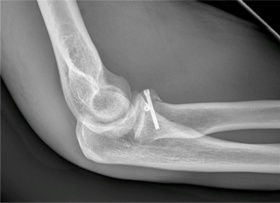

nemocnice v Ústí nad Labem, a Artroskopického centra při ústecké Masarykově nemocnici. Pod vedením Lubomíra Koppa provedli vysoce specializovaný výkon na loketním kloubu. Jednalo se o artroskopicky asistovanou osteosyntézu zlomeniny hlavičky vřetenní kosti, která byla prvním výkonem tohoto typu v rámci české operativy.

„Operovaný sedmadvacetiletý pacient utrpěl při pádu dislokovanou zlomeninu hlavičky vřetenní kosti, která by se standardně řešila technikou krvavé repozice a vnitřní osteosyntézy. Tento operační postup vede často ke ztrátě výživy jednotlivých úlomků kosti, pooperačnímu ztuhnutí loketního kloubu či poranění vřetenního nervu. Pro snížení rizika pooperačních komplikací byl proto zvolen miniinvazivní postup, kdy vlastní repozice úlomků a zavádění osteosyntetického materiálu byly prováděny artroskopicky asistovaně, bez nutnosti otevírat postižený kloub. To bylo umožněno vysokou erudicí týmu v technice artroskopie loketního kloubu, která byla na půdě ústecké kliniky úrazové chirurgie v minulosti provedena více než sedmdesátkrát, a rovněž zkušenostmi s artroskopicky asistovanou osteosyntézou v dalších lokalitách těla jako jsou patní kost, hlezenní kost, holenní kost,“ uvedl k výkonu Lubomír Kopp.

Samotný výkon proběhl bez komplikací, pacient byl propuštěn třetí den po operaci do domácího ošetřování. „Po sejmutí doplňkové sádrové fixace a zahájení rehabilitace dosáhl za šest týdnů takřka plného rozsahu hybnosti v loketním kloubu i předloktí, což lze považovat za mimořádný úspěch a důkaz, že miniinvazivní technika skutečně snižuje riziko pooperační ztuhlosti a poruchy prokrvení kostních úlomků. Vzhledem k použití nejmodernějších osteosyntetických materiálů – zanořených dózovaně kompresních titanových šroubů poslední generace – nebude nutné tyto extrahovat a tím ušetříme pacientovi další operační výkon,“ doplnil Lubomír Kopp.